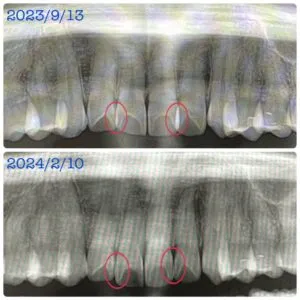

・写真2枚目、3枚目の赤⭕️部分は、重なり合っていた歯の重なりがなくなった箇所